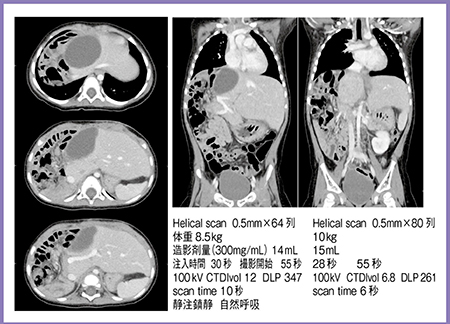

4.肝芽腫

当センターは小児がん拠点病院のため,腫瘍の患児が多く,診断や治療後の効果判定,再発の有無の確認などにCTを撮影する。以前から原則的に単相撮影とし,造影剤1.5mL/kgで撮影しているが,肝静脈や門脈を描出でき,検出能も十分であった。

症例4は,肝芽腫術後,化学療法後の患児で,64列CTと320列ADCTでヘリカルスキャンにて撮影している(図5)。管電圧はともに100kVで撮影しているが,ADCTでは撮影時間が短縮し,CTDIvol,DLPも低下していて,被ばく低減に大きく貢献していると実感できる。

これらの症例からわかるように,CT装置の性能が向上することで,撮影時間短縮,被ばく低減,画質向上,造影剤量減少など,小児検査において多くのメリットを得ることができる。

図5 症例4:肝芽腫術後,化学療法後(2歳)